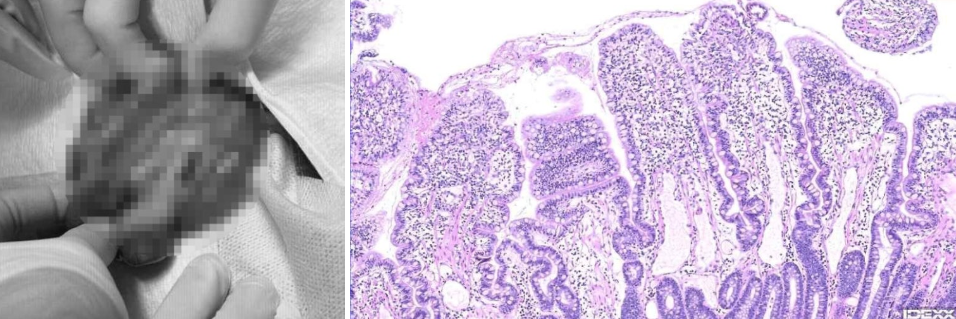

7월 17일 '개복 장 생검 시행'

보다 정확한 진단과 향후 치료 방향 설정을 위해 개복 후 장 전층 생검을 진행했습니다.

병리 검사 결과,

- 만성 림프형질세포성 장염

- 중등도 이상의 림프관 확장증

- 만성 염증 소견

이 확인되었고, 나무는 최종적으로 CIE에 해당하는 만성 장 염증 질환과 PLE를 동반한 림프관 확장증으로 진단되었습니다.